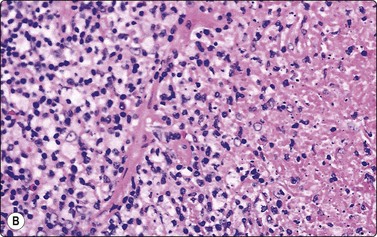

image image

Fig. 5.12 Sinus histiocytosis with massive lymphadenopathy (Rosai-Dorfman disease)

(A) Tissue section showing very large histiocytes harboring many lymphocytes (and some plasma cells) in their cytoplasm, (H&E, IP); (B) Smear showing large histiocytes with intracytoplasmic lymphocytes and plasma cells (MGG, IP).

(Reproduced with permission from van Heerde et al.9)